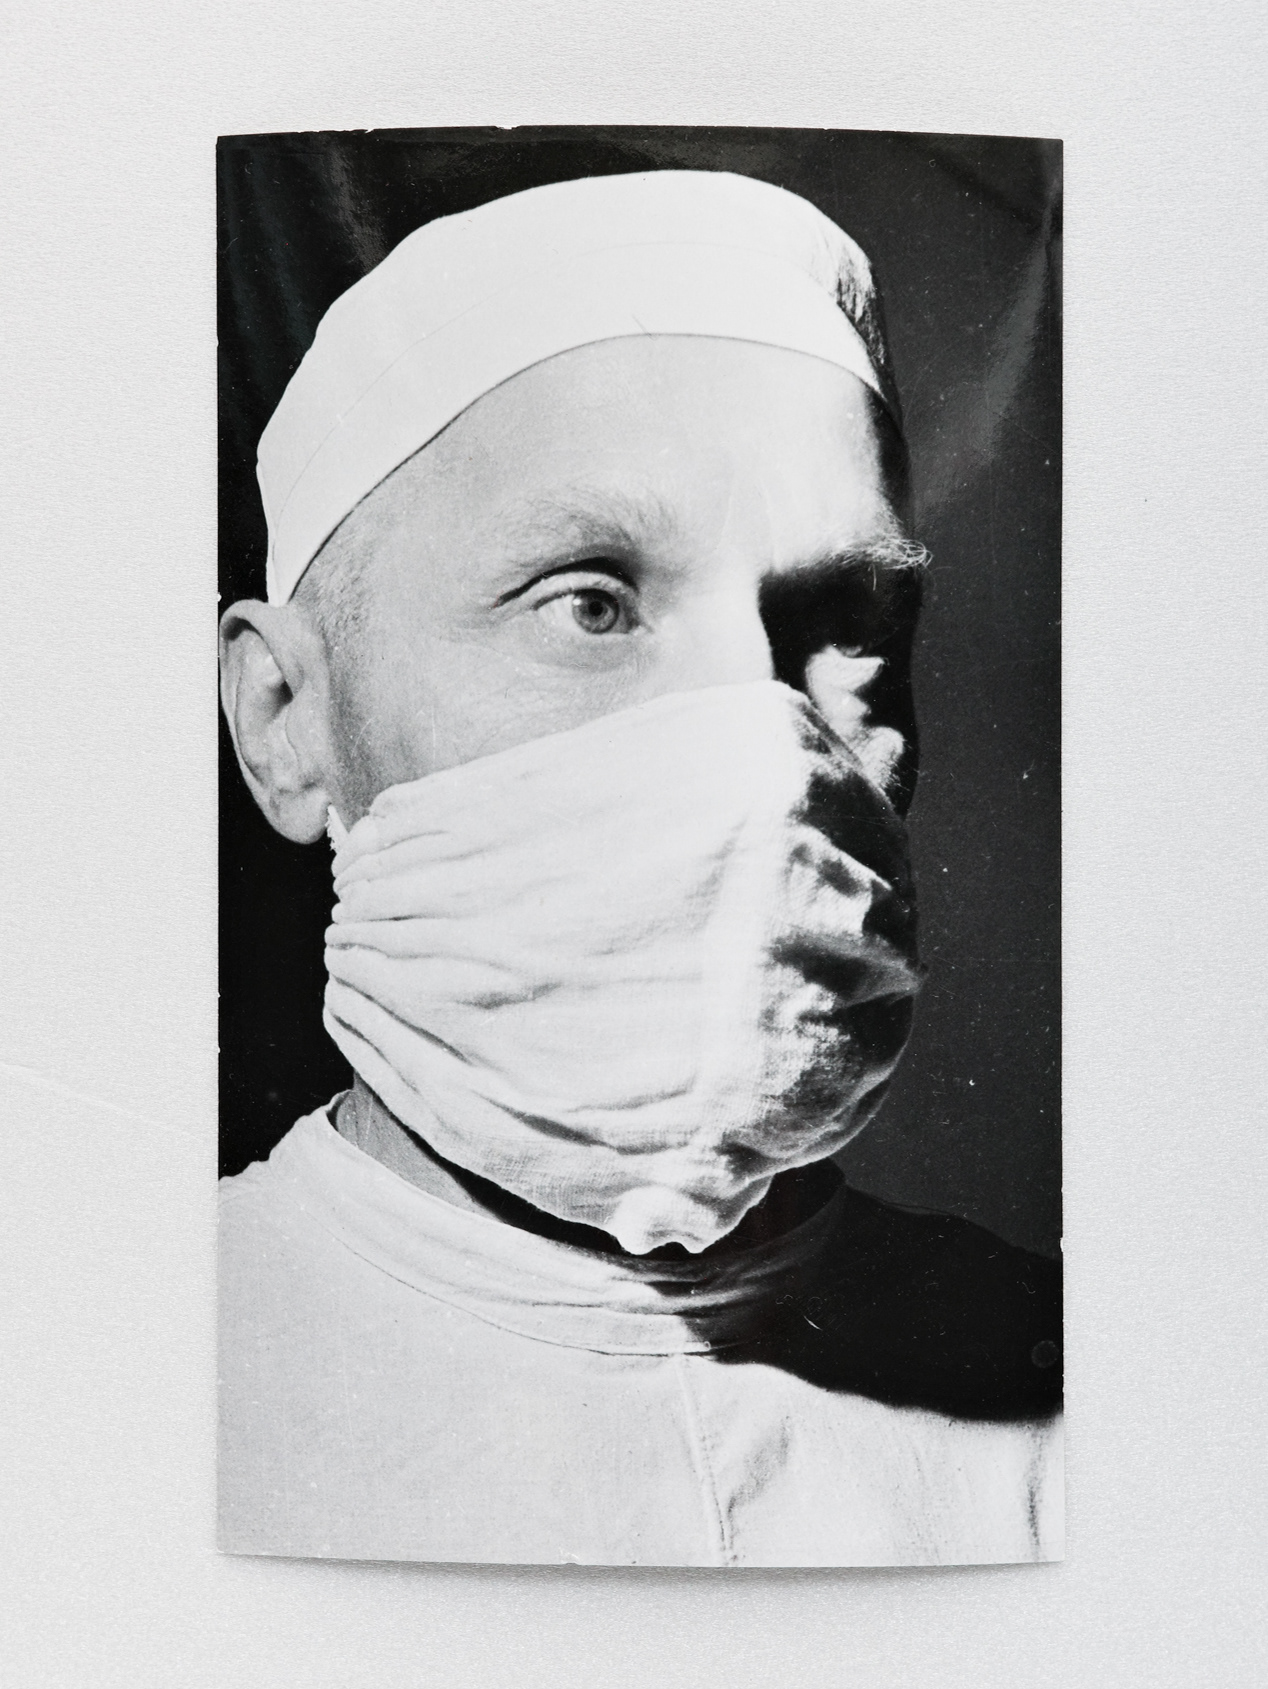

Chornobyl